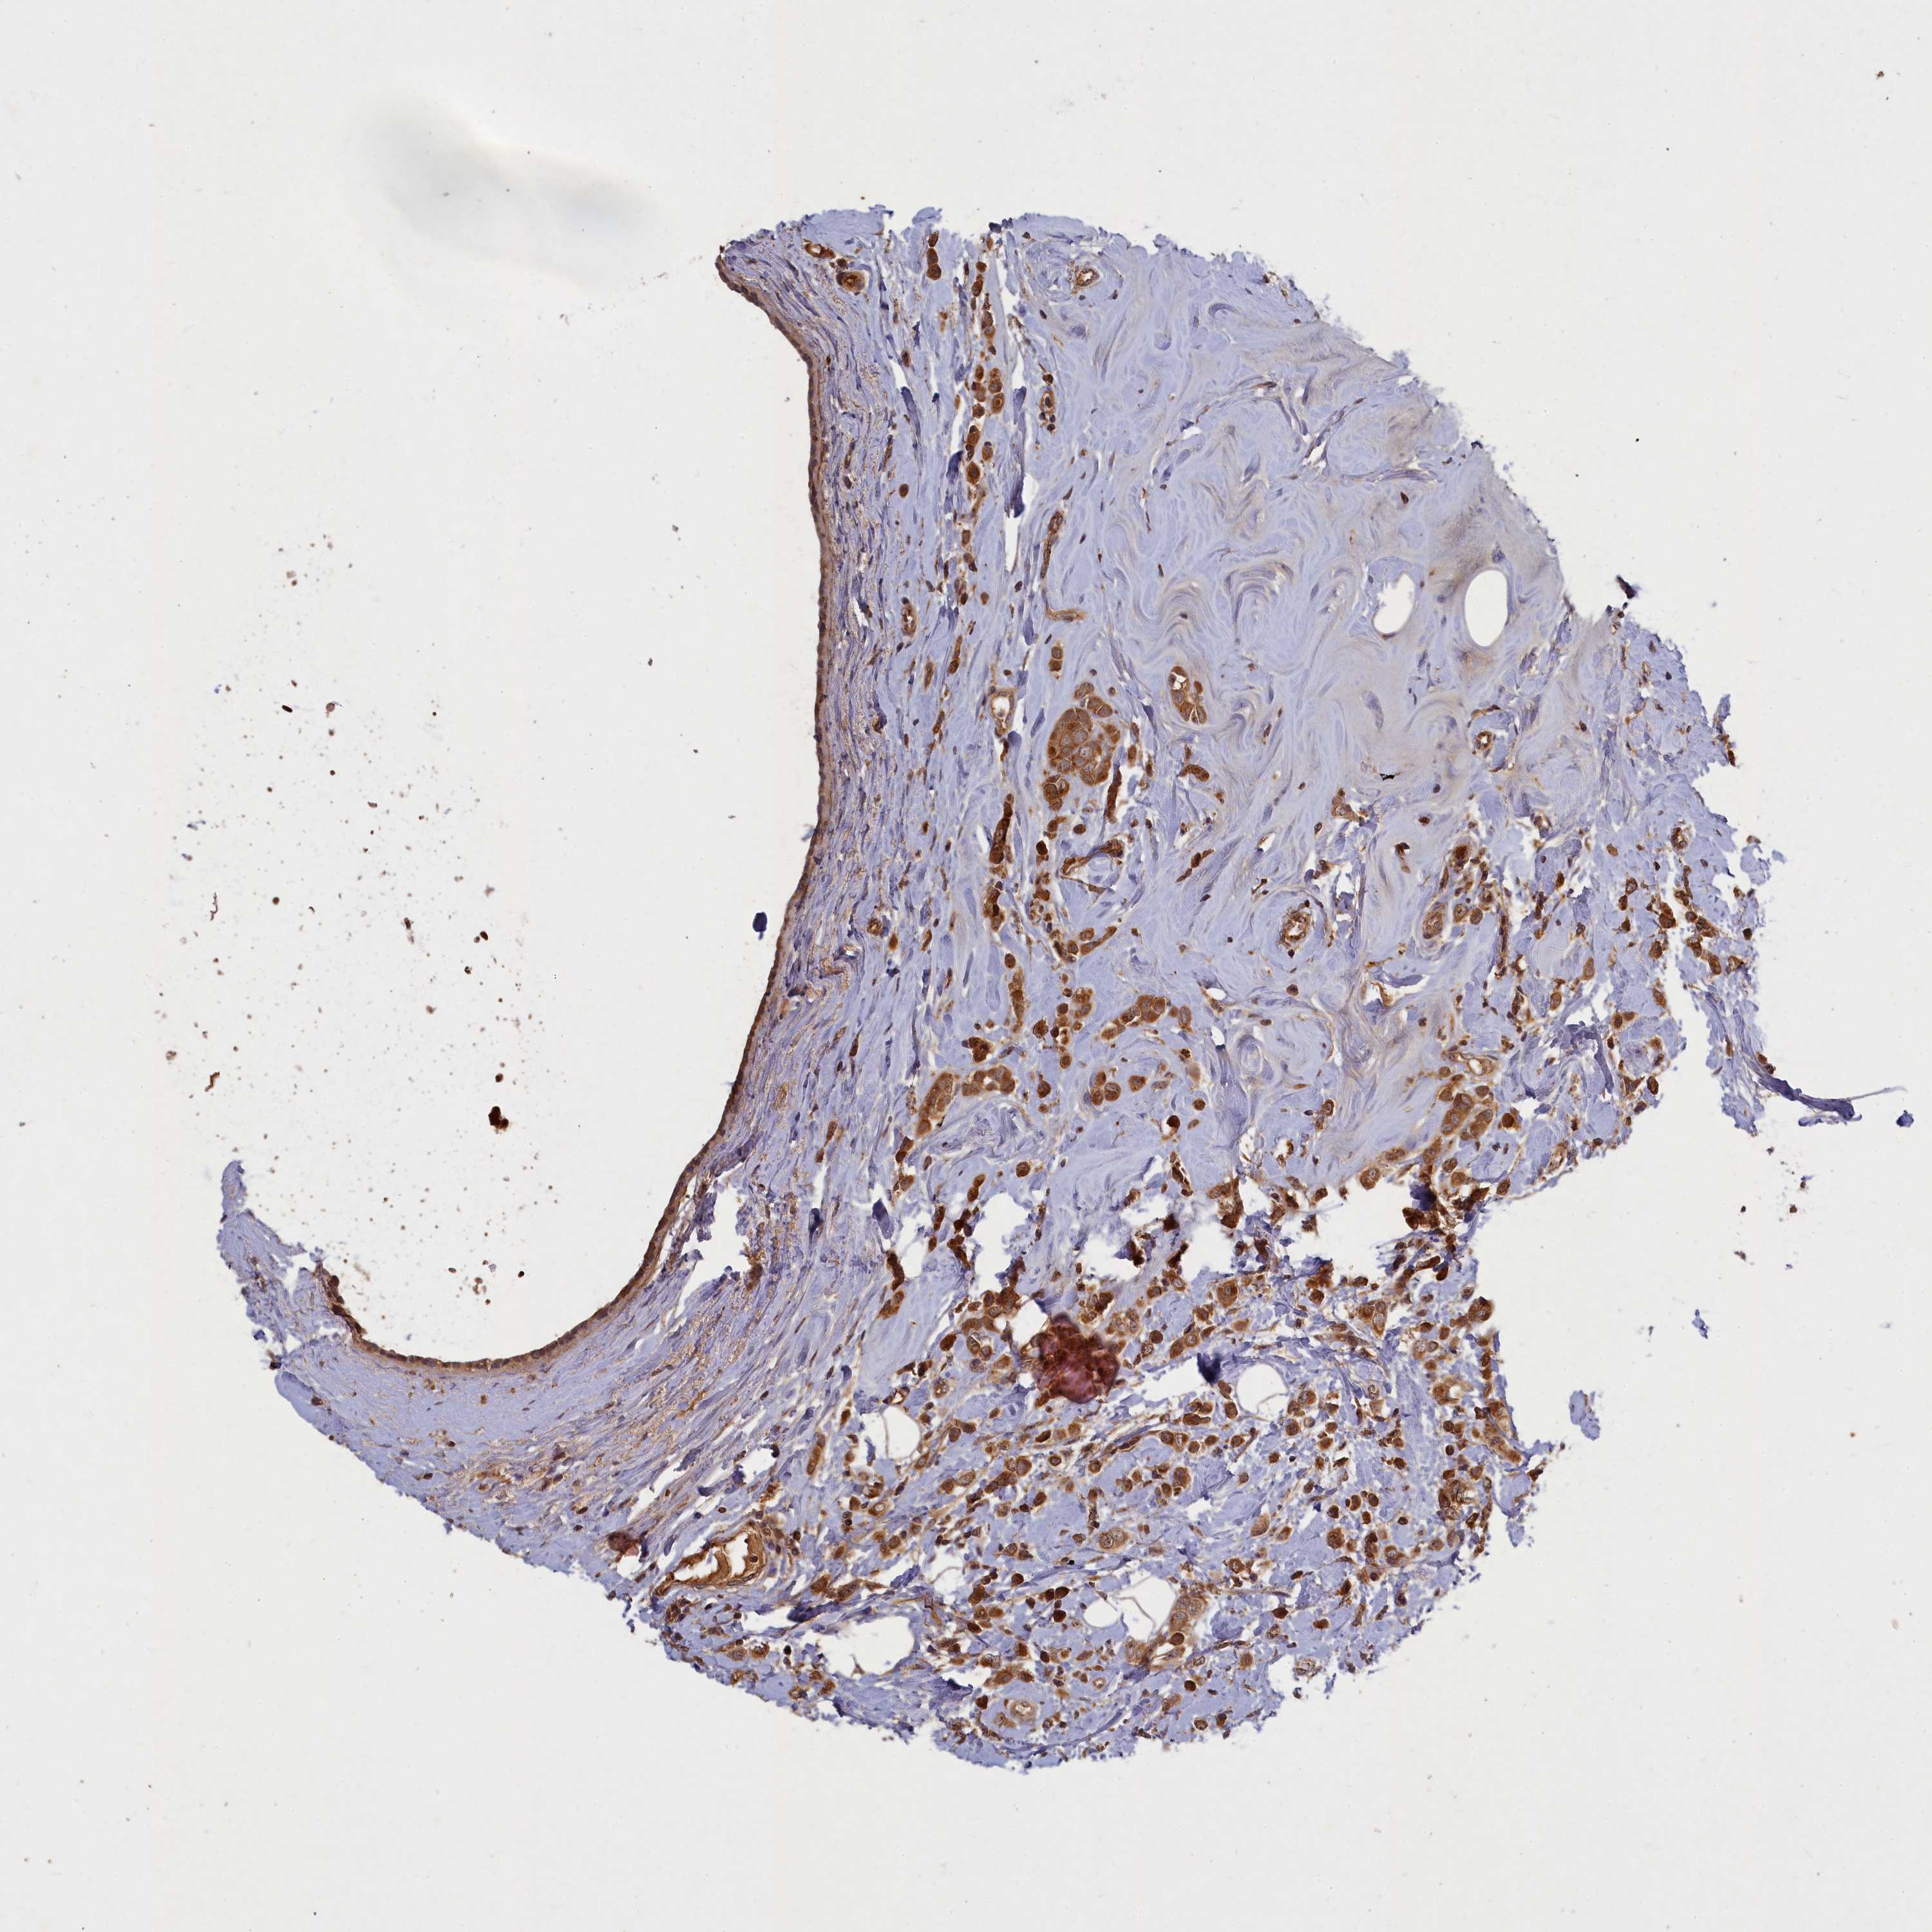

CANCER BREAST CANCER Show tissue menu

BRCA TCGA BRCA VALIDATION PROTEIN EXPRESSION

ANTIBODIES

AND

VALIDATION